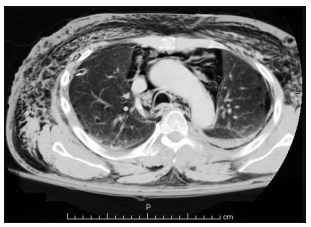

Homem de 18 anos, vítima de colisão moto x

auto há 2 horas, refere apenas muita dor

torácica para respirar, estando estável

hemodinamicamente. Exame físico

direcionado: enfisema de tecido celular

subcutâneo principalmente em região

anterior e lateral do tórax, expansibilidade

simétrica bilateralmente, murmúrio vesicular

presente bilateralmente, sem alteração à

percussão. A TC de tórax é apresentada a

seguir:

Assinale a alternativa correta em relação ao diagnóstico e a conduta adequada nesse caso.